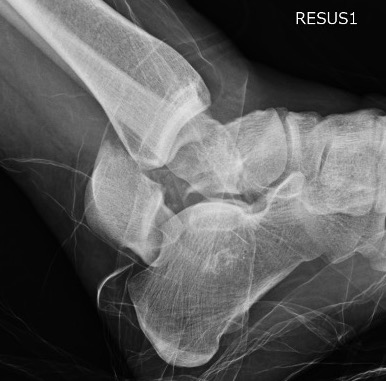

Xray / CT

Ensure no displacement / malalignment

Xrays

| AP | Lateral | Canale View |

|---|---|---|

| Entry point of the screws |

Evaluate neck reduction

|

Evaluates the neck reduction |

Lateral off articular surface Medial through articular cartilage |

Depth of screws |

Beam angled 75o to foot Foot 15o pronated |